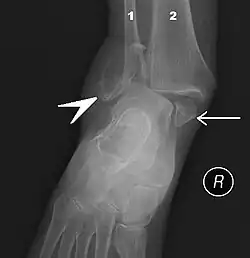

The initial evaluation of suspected ankle pathology is usually by projectional radiography ("X-ray").

Varus or valgus deformity, if suspected, can be measured with the frontal tibiotalar surface angle (TTS), formed by the mid-longitudinal tibial axis (such as through a line bisecting the tibia at 8 and 13 cm above the tibial plafond) and the talar surface.[25] An angle of less than 84 degrees is regarded as talipes varus, and an angle of more than 94 degrees is regarded as talipes valgus.[26]

For ligamentous injury, there are three main landmarks on X-rays: The first is the tibiofibular clear space, the horizontal distance from the lateral border of the posterior tibial malleolus to the medial border of the fibula, with greater than 5 mm being abnormal. The second is tibiofibular overlap, the horizontal distance between the medial border of the fibula and the lateral border of the anterior tibial prominence, with less than 10 mm being abnormal. The final measurement is the medial clear space, the distance between the lateral aspect of the medial malleolus and the medial border of the talus at the level of the talar dome, with a measurement greater than 4 mm being abnormal. Loss of any of these normal anatomic spaces can indirectly reflect ligamentous injury or occult fracture, and can be followed by MRI or CT.[27]